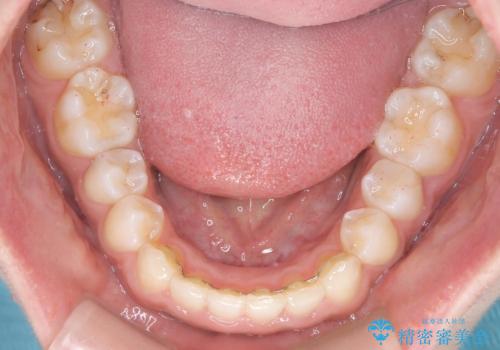

- 患者様は、ディープバイト(深い噛み合わせ)と、咬合平面の左下がりが気になるとのことでご来院されました。診断の結果、非抜歯で治療可能と判断し、透明なマウスピース型矯正装置「インビザライン」を用いる方針としました。治療では、歯列全体の調整を行いながら、咬合平面の水平化を重点的に進める計画を立案しました。2年間で計画的にマウスピースを交換し、左右のバランスと噛み合わせの改善を目指しました。

ディープバイトの矯正は、噛み合わせが深くなりがちなため、細心の注意を払いながら進める必要があります。本症例では、奥歯の高さを調整しつつ前歯の噛み合わせを浅くすることで、全体の咬合バランスを整えました。また、咬合平面の左下がりを修正する過程で、歯列に不均等な力がかからないよう、インビザラインのアタッチメント配置を最適化しました。患者様には装着時間を守っていただき、治療が計画通り進むよう協力をお願いしました。治療終了後には、リテーナーを装着して安定性を確保しました。